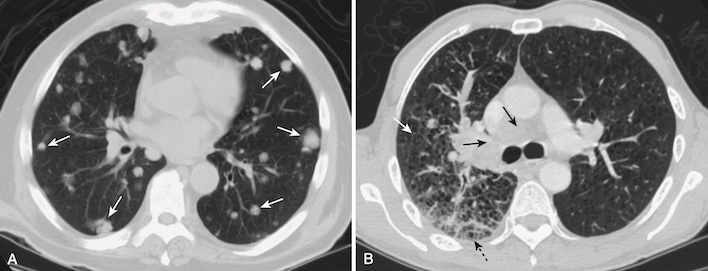

- Bệnh phổi mô kẽ tạo ra những cấu trúc có thể được coi là “phần tử” (“particles”) bệnh rời rạc xuất hiện trong mạng lưới kẽ phong phú của phổi (Hình 8 ).

- Các “phần tử” bệnh này có thể được đặc trưng hơn nữa là có ba dạng biểu hiện:

- Bệnh kẽ lưới (reticular) biểu hiện như một mạng lưới các đường kẽ (xem Hình 8, A).

- Bệnh kẽ hạt (nodular) biểu hiện dưới dạng các chấm (xem Hình 8, B).

- Bệnh kẽ lưới hạt có cả các đường và các chấm (xem Hình 8, C).

- Những “phần tử” bệnh lý kẽ này có xu hướng không đồng nhất, tách biệt với nhau bởi những vùng phổi được thông khí bình thường.

- Các bờ của bệnh phổi kẽ rõ nét hơn so với các ranh giới của bệnh khoang chứa khí (thường không phân biệt rõ).